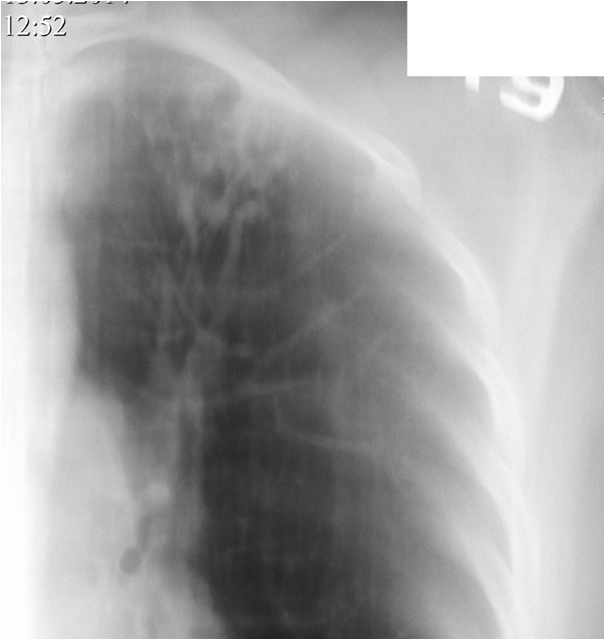

о картине жалоб информацией не располагаю ввиду старости рентгеновских снимков

Тип: Клиническое наблюдение

Область: Грудная клетка и верхние дыхательные пути

Модальность: Rg

Дата: 09.12.2019 - 19:40